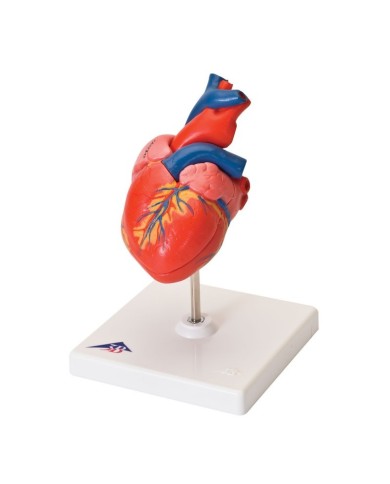

Su Base, staccabile

Su base removibile

Modello anatomico di cuore, ingrandito 2 volte, su cavalletto